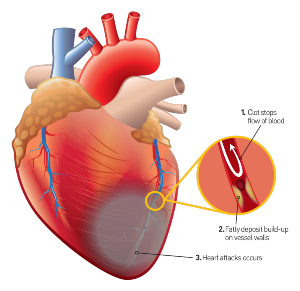

Las pequeñas arterias encargadas de alimentar el músculo cardíaco, se ven deterioradas, estas son las que soportan la presión arterial elevada durante la evolución de la enfermedad hipertensiva.

Las pequeñas arterias encargadas de alimentar el músculo cardíaco, se ven deterioradas, estas son las que soportan la presión arterial elevada durante la evolución de la enfermedad hipertensiva.

Parece que las estructuras celulares que componen el “endotelio” (la capa de tejido que se ubica en el interior de las arterias) sufren “escoriaciones microscópicas” que favorecen la acumulación de grasa y plaquetas con la subsecuente “aterosclerosis”.

Además, esta lesión endotelial causa inflamación local que, a la larga contribuye a empeorar la formación de “placa de ateroma”.

A consecuencia de la enfermedad de estas arterias pequeñas “arteriopatía coronaria aterosclerótica” ocurre disminución y hasta obstrucción del flujo sanguíneo hacia las fibras del músculo cardíaco causando muerte celular: Infarto.